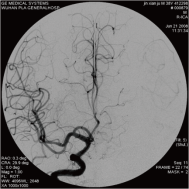

右侧颈内动脉后交通动脉瘤栓塞术前 左椎动脉造影 示左椎动脉夹层动脉瘤: 左椎动脉发出小脑后下动脉处呈囊性扩张,动脉瘤远端血管狭窄